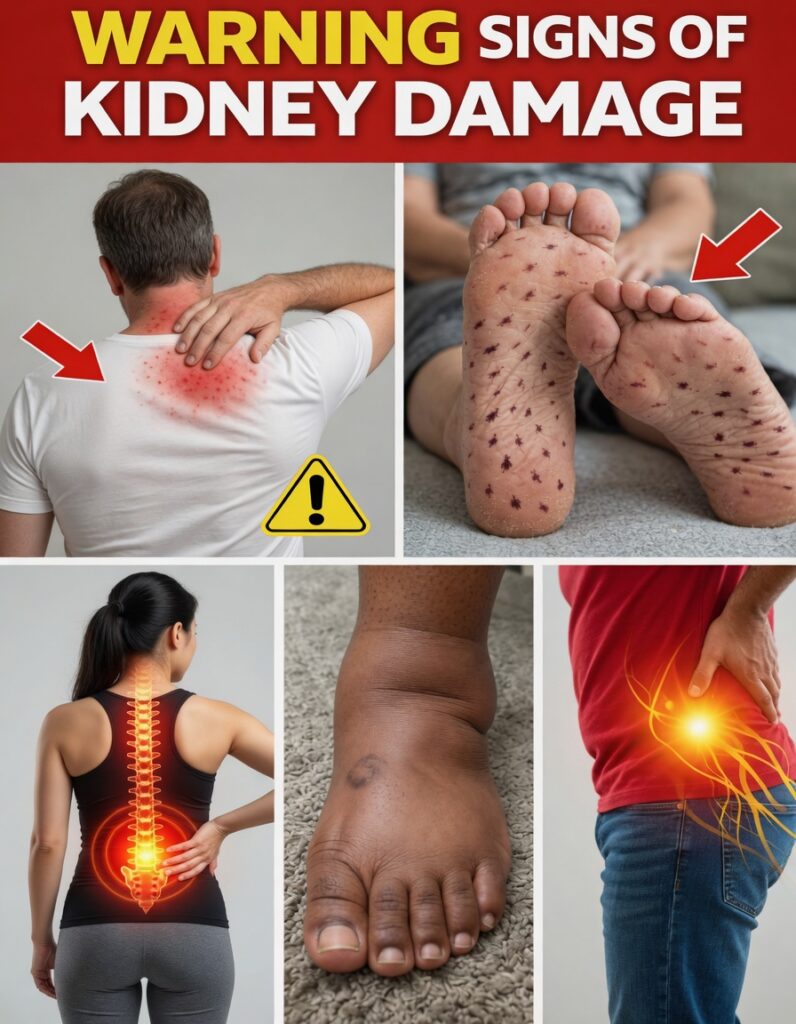

2. Itchy or Extremely Dry Skin

Relentless itching—especially on the back, arms, or feet—that doesn’t improve much with moisturizers can be linked to changing kidney function. When the kidneys are not filtering properly, waste products and mineral imbalances can irritate nerve endings in the skin.

Common patterns include:

- Itching that feels “deep” rather than only on the surface

- Rough, dry patches that keep coming back

- Irritation on the soles of the feet or lower legs

Studies have connected itchy, dry skin and changes in skin texture with reduced kidney function.

3. Swelling in Feet, Ankles, and Legs

Puffiness in the lower legs, ankles, or feet—especially if your socks leave deep marks—is a classic sign of fluid retention. When kidneys struggle to remove excess fluid and sodium, swelling (edema) often appears in the lower body.

You may notice:

- Skin that holds a temporary dent after pressing it with a finger

- Shoes feeling tighter as the day goes on

- Heaviness or stiffness in the legs

1. Persistent Back or Side (Flank) Pain

A slow, aching discomfort in your lower back or along your sides (flanks) that doesn’t fade with rest may be a sign your kidneys need attention.

Unlike a typical muscle strain from lifting or exercise, this pain often:

- Feels deeper, not just on the surface

- Lingers or returns regularly

- May affect your posture or make everyday movements uncomfortable

13. Nerve Pain, Tingling, or Numbness in Legs and Hips

Tingling, burning, numbness, or shooting pain in the legs and hips can appear when kidney disease affects nerve health. These sensations may:

- Radiate from the lower back into the hips and thighs

- Make walking or standing uncomfortable

- Come and go, or steadily worsen over time

This pattern often mirrors the highlighted areas seen in medical diagrams of nerve pain and may be linked to chronic kidney issues, especially in people with diabetes.